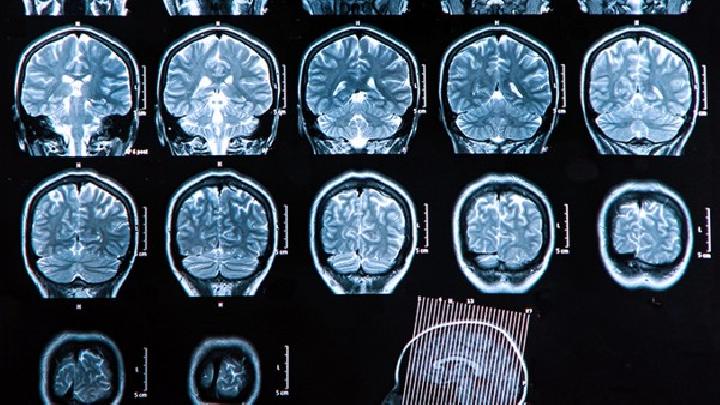

新生儿脑瘫需通过体格发育评估、神经反射检查、影像学扫描及基因检测综合诊断。 1、发育评估 观察抬头翻身等动作是否...